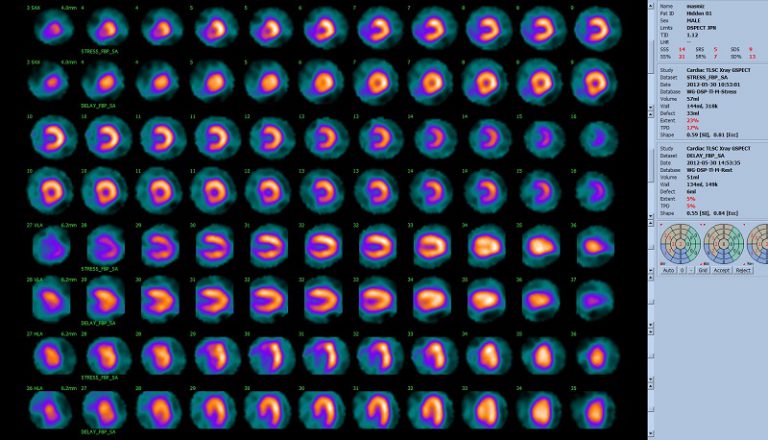

核医学検査では、特定の臓器や組織に集まりやすい性質を持った微量の放射性医薬品を体内に投与し、臓器や体内組織に集まる様子を画像として捉えることができます。CT検査やMRI検査が、臓器の形態情報を表しているのに対し、核医学検査は臓器や組織の形態だけでなく、機能や代謝状態などを評価することができます。 従来の装置は、ヨウ化ナトリウム(NaI)を結晶化した検出器を使用しているのに対し、当院の装置は高感度・高解像度CZT半導体検出器を用いているため、少量の放射性医薬品の投与で高画質の画像を短時間で得ることができます。これまでの機器と比べて10倍の感度と2倍の空間分解能を有しています。従来は寝た状態で検査を行うため、腰の痛い患者さんや背中の曲がった患者さんには苦痛の伴う検査でしたが、D-SPECTは寝た状態だけでなく、座った姿勢でも検査が施行できるため、楽に検査を受けてもらえるようになりました。 VERITONは、全身の撮影ができる装置ですが、心臓は専用装置と同等の画像を得る事ができます。

D-SPECT Cardio Generation 2.0(全世界1号機)

全身用半導体ガンマカメラ VERITON(国内1号機)

下記画像の左が従来型SPECT、右がD-SPECTです。